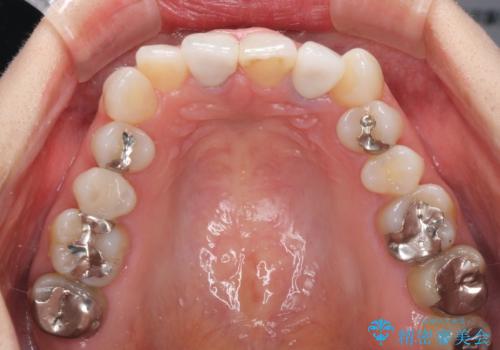

- 20年ほど前に被せた前歯のメタルボンドクラウンの色合いを気にして来院された患者様です。

2歯をオールセラミッククラウン(ジルコニアクラウン)にて補綴することとしました。

裏打ちが金属の場合、どうしても金属色を遮蔽しないとならないため、透明感のない色合いとなってしまいます。

土台の金属はグラスファイバーを含有したものに、クラウンの土台は強化セラミックとすることで、自然な前歯に仕上がりました。